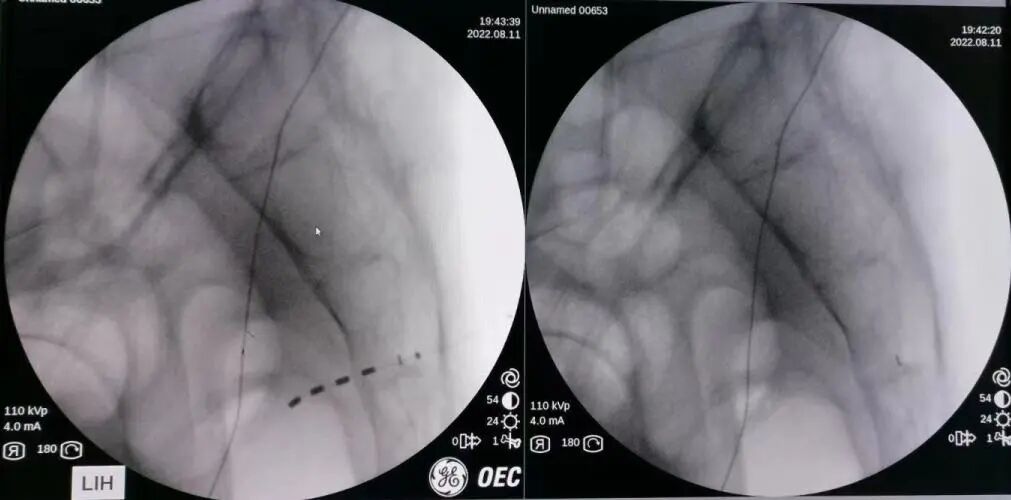

2022年8月11日,在李碧锦主任的殷切指导下,李超文副主任携团队李军副主任医师、杨家冠医师作为手术助手为彭先生进行了 I 期电极植入手术,术中电极植入位置精准,各位点运动应答、感觉应答明显,测试效果满意。术后开机当天彭先生自觉效果良好,目前处于测试体验阶段,期待彭先生从该疗法中获益更多。

电极植入位置精准